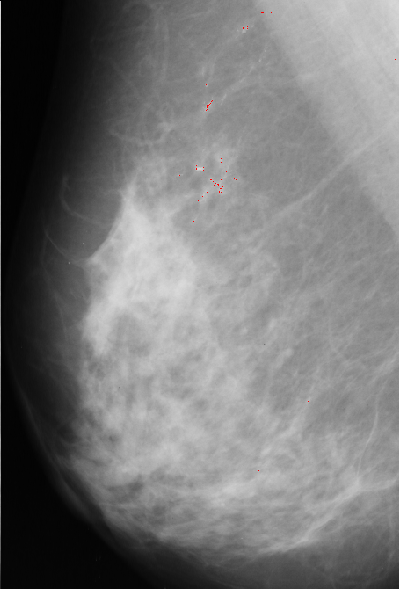

Median filter approach is based on assumption that microcalcification are small spots with higher intensity then surrounding background. First we apply median filter to bright area of the original image. Median filter eliminates small isolated spots including microcalcifications. Next step is to bring them back by substracting filtered image from original one. Since we are only interested in spots brighter than background we keep only positive resulting values and set other to zero. Our next step is to match resulting image with 5x5 template. It has bell shape with value of 1 at the central point, which we expect to have a best fit at the position of microcalcification.

Template, multiplied with pixel value at current position, is substracted from median filtered image. The results are normalized, thresholded and added to

original image to point to possible position of microcalcification.

A result of this approach is: